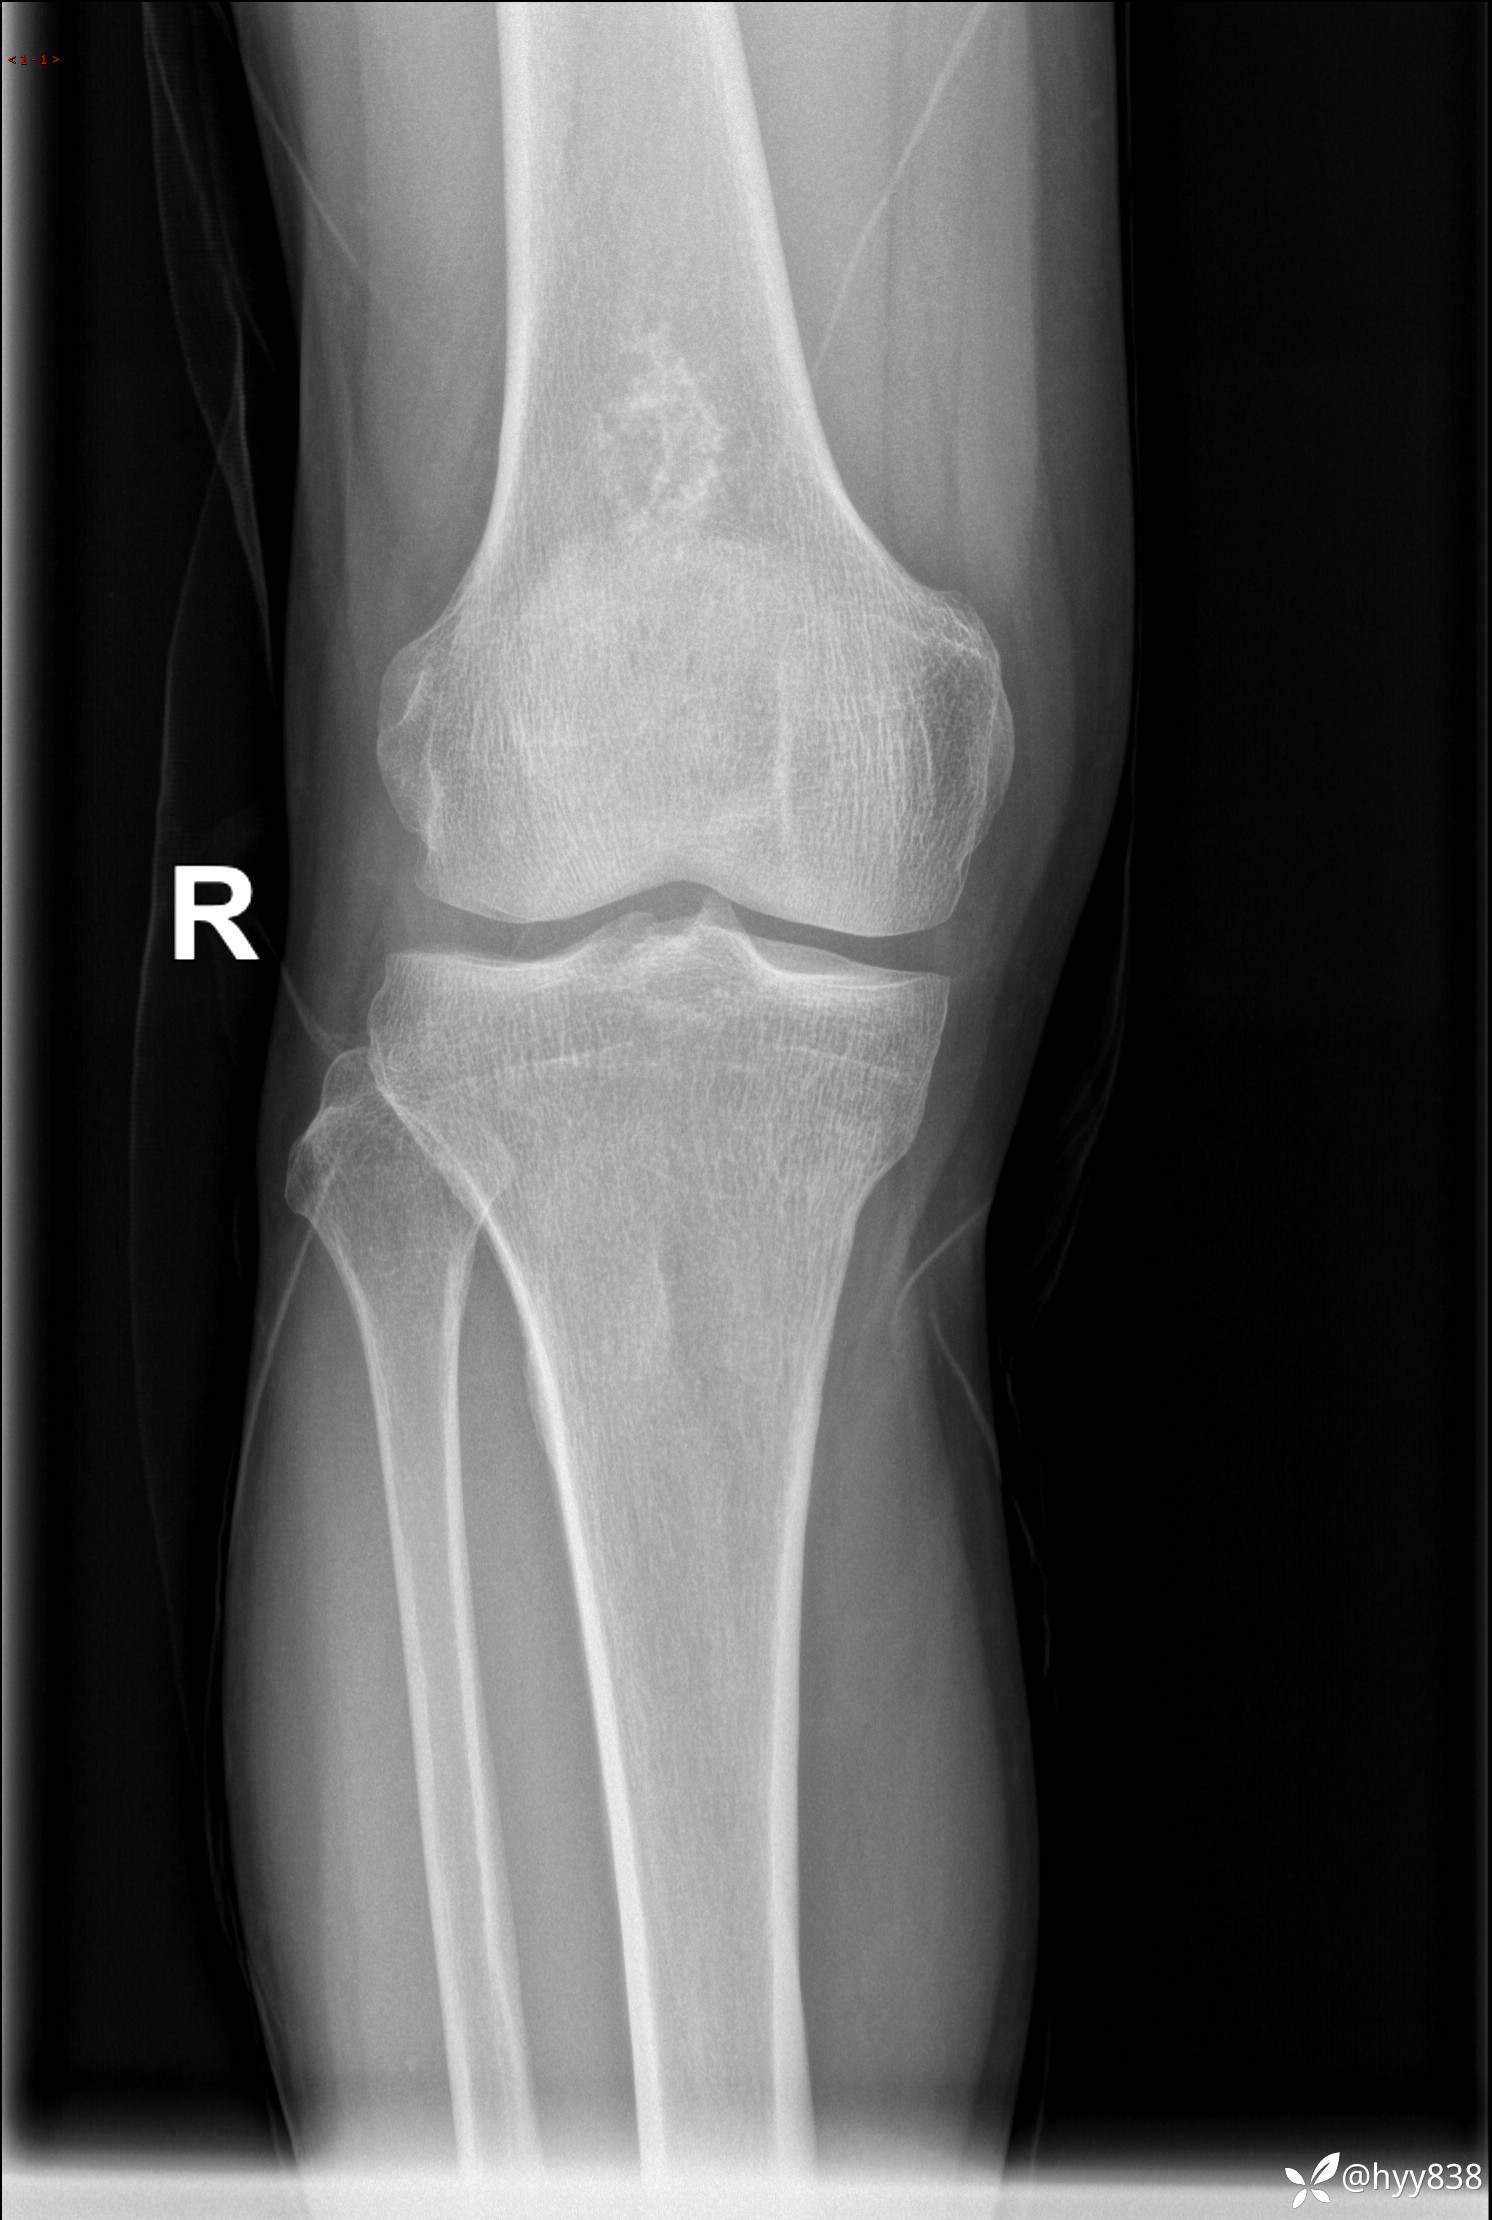

CT

img